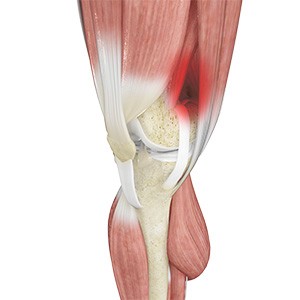

Patellar Tendinitis

Patellar tendinitis, also known as "jumper's knee", is an inflammation of the patellar tendon that connects your kneecap (patella) to your shinbone. This tendon helps in extension of the lower leg.